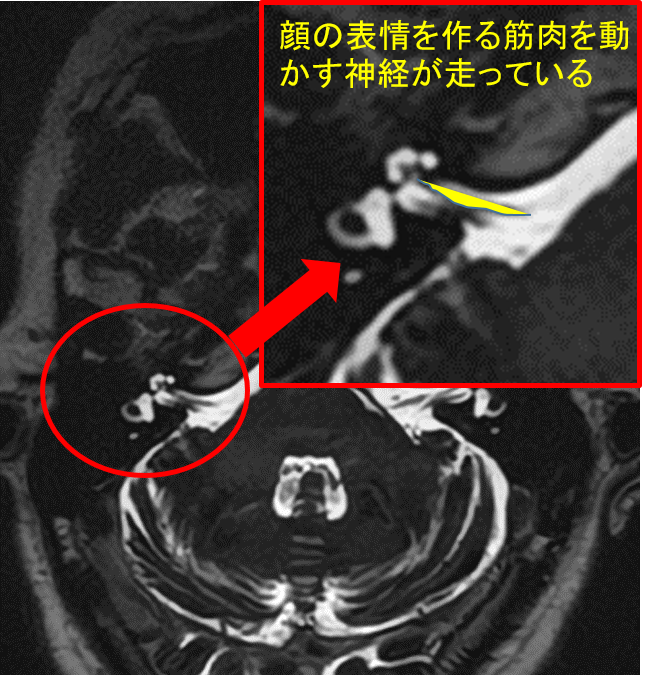

顔面けいれんの確定診断と治療方針の決定には、MRI検査が極めて重要です。 当院では、3D-FIESTA(フィエスタ)やCISS(キス・シス)といった、神経と血管を非常に鮮明に映し出す特殊な撮像法を用いて、以下の情報を正確に把握します。

顔面痙攣|MRIで何をみる?

- 責任血管の特定

- 神経を圧迫している血管の種類・位置・方向

- 圧迫部位の確認

- 顔面神経のどの部分が圧迫されているか

これらのMRI画像を3次元で再構成することで、神経と血管の位置関係を立体的な「設計図」として捉え、診断の精度を高めるだけでなく、安全な手術計画にも繋げています。

主訴:数年前からの、”右まぶた”から”頬”にかけてのピクつき

”右まぶた”から”頬”にかけてのピクつきということでMRI検査を施行すると…